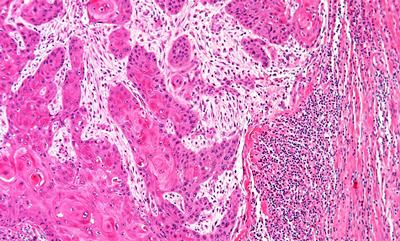

Tratamentul de imunoterapie pentru cancer valorifică puterea sistemului imunitar de a lupta împotriva cancerului, succesul său fiind dependent de cantitatea și capacitatea limfocitelor de a combate celulele maligne. Răspunsul slab sau ineficient la tratament al organismului este cauzat de blocarea limfocitelor la marginea tumorii. Echipele de cercetători au descoperit că fibroblastele asociate cancerului, considerate celule normale ale organismului, sunt deturnate de celulele canceroase și folosite pentru a le proteja de atacul sistemului imunitar. Fibroblastele corupte de celulele canceroase protejează tumorile de atacul limfocitelor și opresc imunoterapia, devenind o barieră pentru celulele maligne.

foto: Celule canceroase - punctele negre din partea dreaptă reprezintă limfocite oprite de fibroblaste asociate cancerului (University of Southampton)